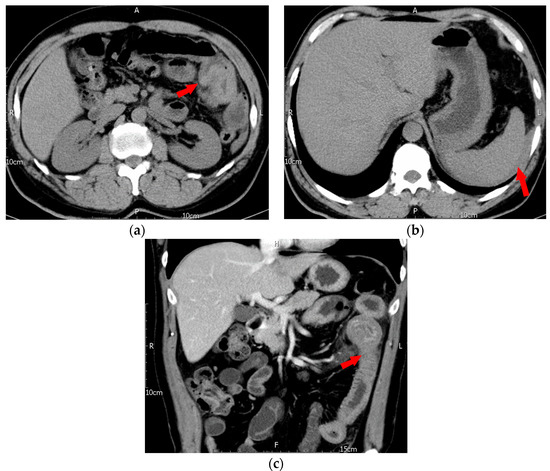

5.4. Image Findings